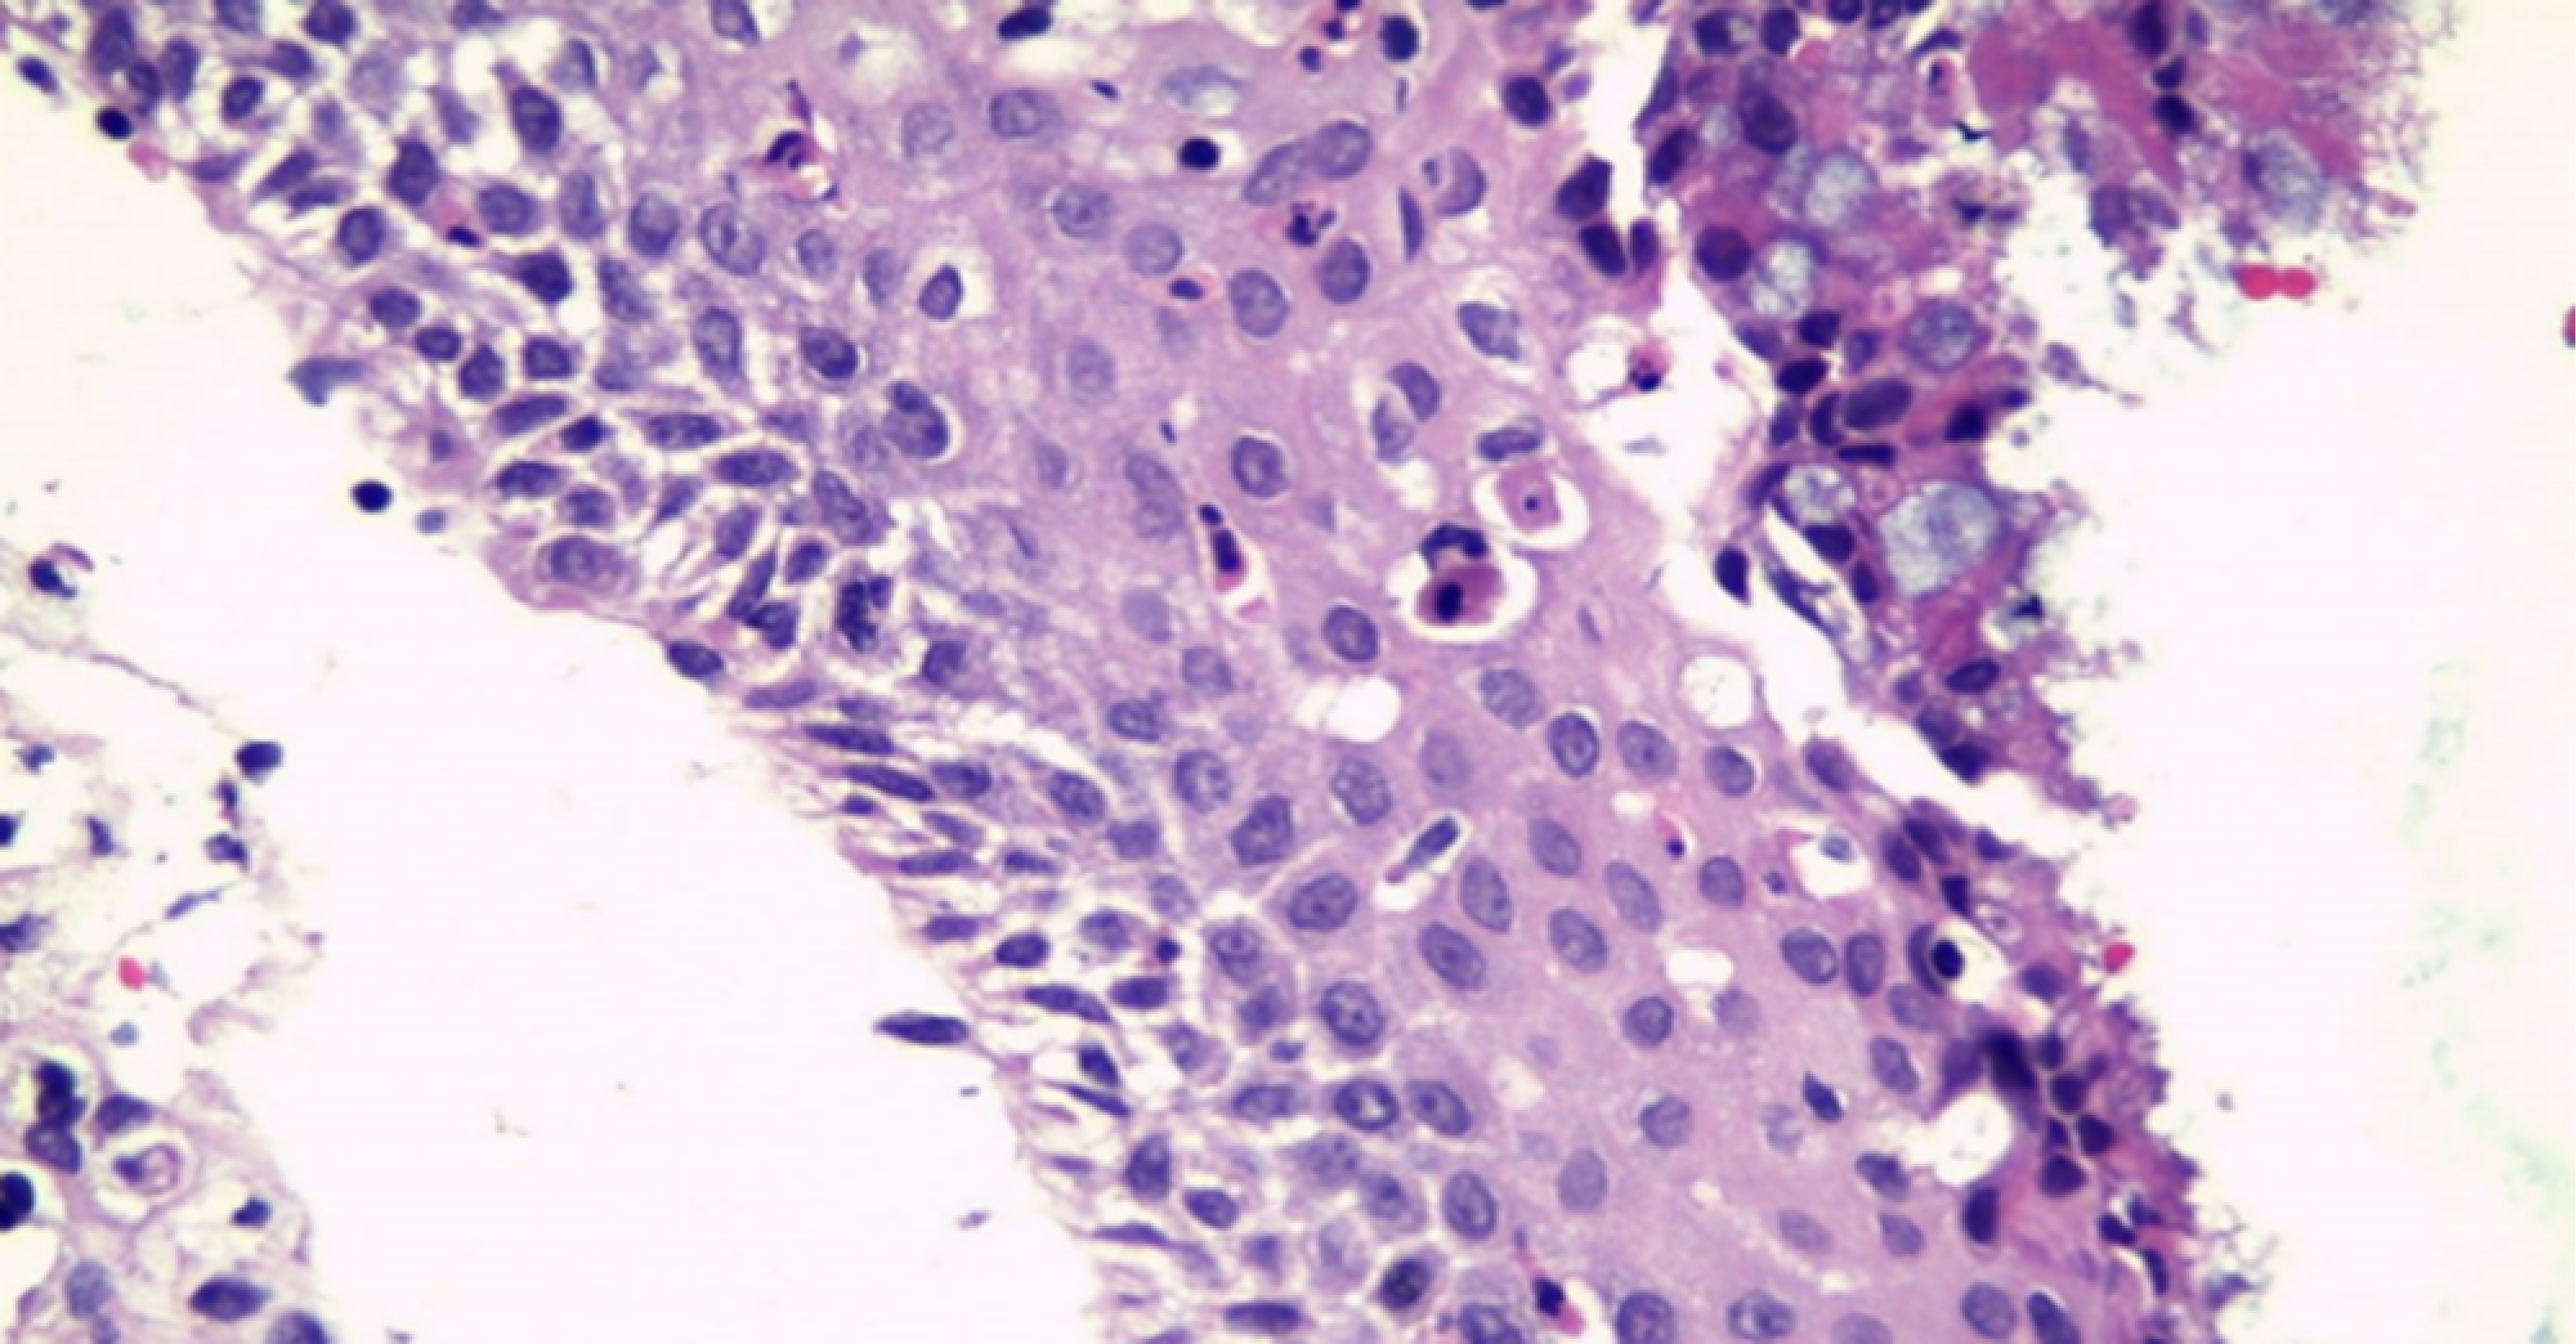

La paciente fue programada de forma electiva para abordaje transesfenoidal más resección de la lesión, la cual se realizó el día 28 de febrero de 2022 (Figura 6), y se encontraron como hallazgos microquirúrgicos lesión mucinosa transparente aspirable de consistencia gelatinosa, la cual se mandó a estudio histopatológico donde se hallaron características que se muestran en las Figuras 3, 4 y 7.

Histopatología. El estándar de oro es el análisis histopatológico. A veces, tras el drenaje del quiste, puede ser difícil obtener una muestra quirúrgica de la pared quística. En el análisis rutinario de hematoxilina y eosina, se muestra un epitelio columnar o cuboidal simple con células caliciformes ciliadas o mucinosas. También se observan con frecuencia células columnares pseudoestratificadas.

Figura 4

Figura 7